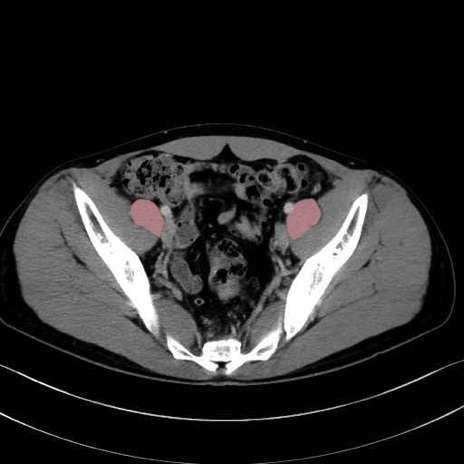

2. 腸腰筋群と骨盤底筋

大腰筋 (Psoas major)

腸骨筋 (Iliacus)